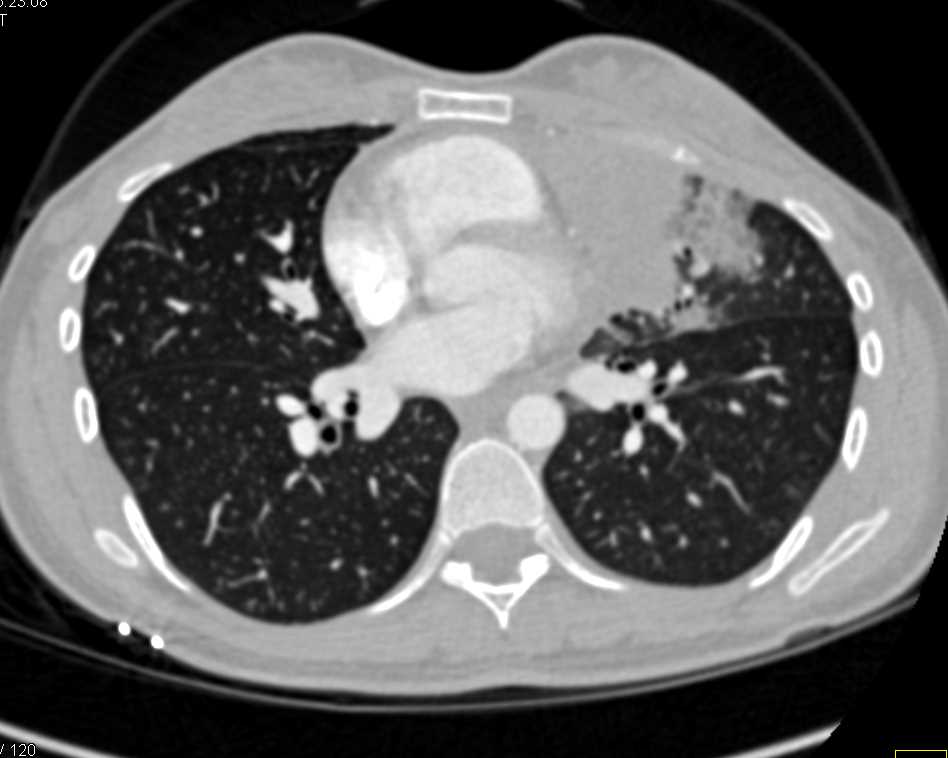

From www.ctisus.com

Lymphoma Involves Mediastinum and Pericardium Chest Case Studies Can A Chest X Ray Miss Lymphoma The best way to diagnose lymphoma is to perform a biopsy of a lymph node. This test isn’t needed if a ct of the chest is done. Patients with lymphoma often have ct scans of the neck, chest, abdomen, and pelvis to find out how many lymph nodes are involved, how large they are, and whether internal organs are affected. Can A Chest X Ray Miss Lymphoma.